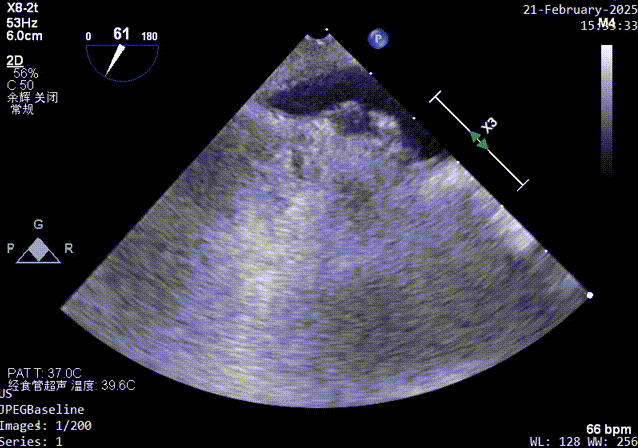

color超声影像

经食道超声:房间隔卵阙窝边缘见卵圆瓣闭合不佳,可见一隧道样缝隙,长约16mm,左房面约1.6mm,右房出口约1.0-2.3mm,X-plane短轴切面而测得宽度约10mm,CDFI可在该处探及左向右过血流。原发隔卵圆瓣厚约1.3mm,继发隔厚度约4.4mm,右房面出口距主动脉根部约7mm,距上腔静脉入口约19mm。